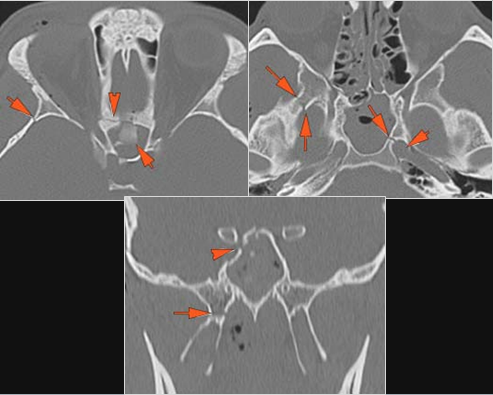

21-year-old male in the emergency room following an altercation with possible orbital or other facial fractures.Exam

There is evidence of herniated intra-orbital fat. |

Yes | NA |

The extraocular muscles are swollen, infiltrated or herniated into a fracture site. |

There is evidence of bony injury along the walls and/or floor of the orbit. |

The mesial naso-orbito-ethmoid complex is fractured. Specifically, there is bony injury of the nasal bones or the frontal process of the maxilla and the medial walls of the orbit are abnormal. |

Orbital floor fracture on the left with significant entrapment of orbital fat and entrapment of the inferior rectus muscle in a likely trapdoor type mechanism and minimally displaced fractures of the medial orbital wall and nasal bones.

Contact ER providers verbally about the finding of likely “trapdoor” herniation of the inferior rectus muscle and strongly suggest the ophthalmology and facial trauma on call be consulted emergently with regard to this finding.